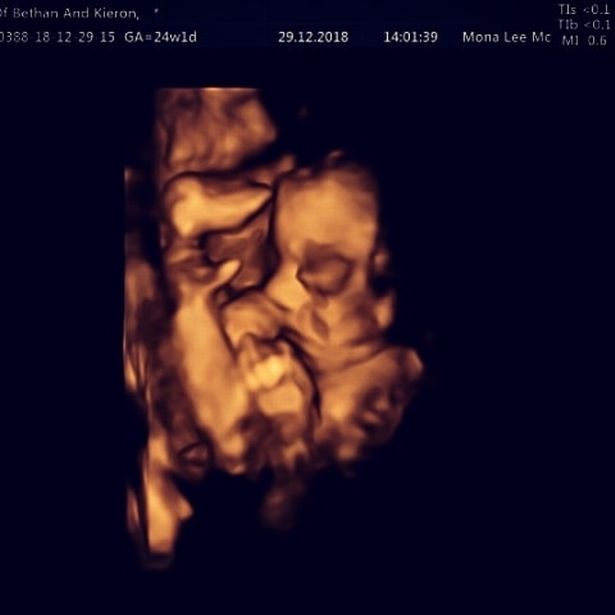

▼最後在懷孕24周時終於接受手術,讓來自倫敦和比利時的醫生負責動手術。

▼醫生首先幫Bethan做全身麻醉,然後在子宮位置開刀將胎兒取出。

▼接著就開始調整好胎兒的脊柱位置,還要加強保護,確認完成所有步驟後再把寶寶放回母體繼續孕期。根據醫生解釋,這項手術的主要目的是防止情況惡化,只有這樣才能在寶寶出生後再動其他脊柱手術,讓效果更佳。